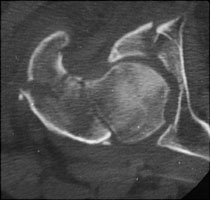

- Click on the image for a larger versionBAxial CT. This demonstrates a fracture of the neck of the femur and the anterior column of the acetabulum.